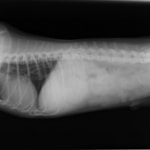

4歳 アメリカンショートヘアー

主訴:3日前から嘔吐が続き、食欲も落ちてきたのこと。

対症療法(症状に対する治療)に反応しないため、精査を実施。

一般血液検査:問題なし

単純レントゲン検査:胃内ガス陰影・腸内ガスが少量認められる。

嘔吐が改善しないため、消化管バリウム造影検査を実施。

以下、

消化管バリウム造影レントゲン

バリウム造影3時間経過するも、胃内からバリウム排泄なく同日内視鏡検査を実施。

内視鏡検査結果:内視鏡下にて、バスケット鉗子を用いて摘出。

症例は、机の上に置いていたピスタチオのお菓子を誤飲していました。その後の経過は良好です。本症例は、内視鏡下にて摘出ができましたが、球状・立体などの大きな異物は、腸の途中で詰まりやすく、内視鏡下での摘出が困難な場合もあります。その際は、開腹下にて腸内の異物を摘出しなくてはなりません。動物たちは、思わぬ物を誤飲することがあります。お留守番時・就寝時は、誤飲をしやすい時間帯ですので注意しましょう。